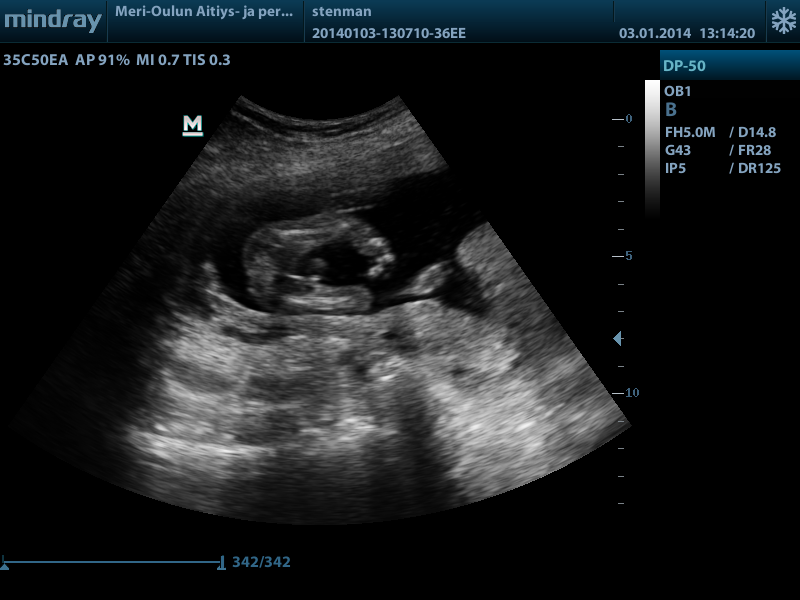

https://www.dropbox.com/s/2papaybdya...14410005OB.AVI

Hi everyone

I share four pictures and a video. The video is filmed from the underside of the baby.

Please, does anyone know, I really have no idea?